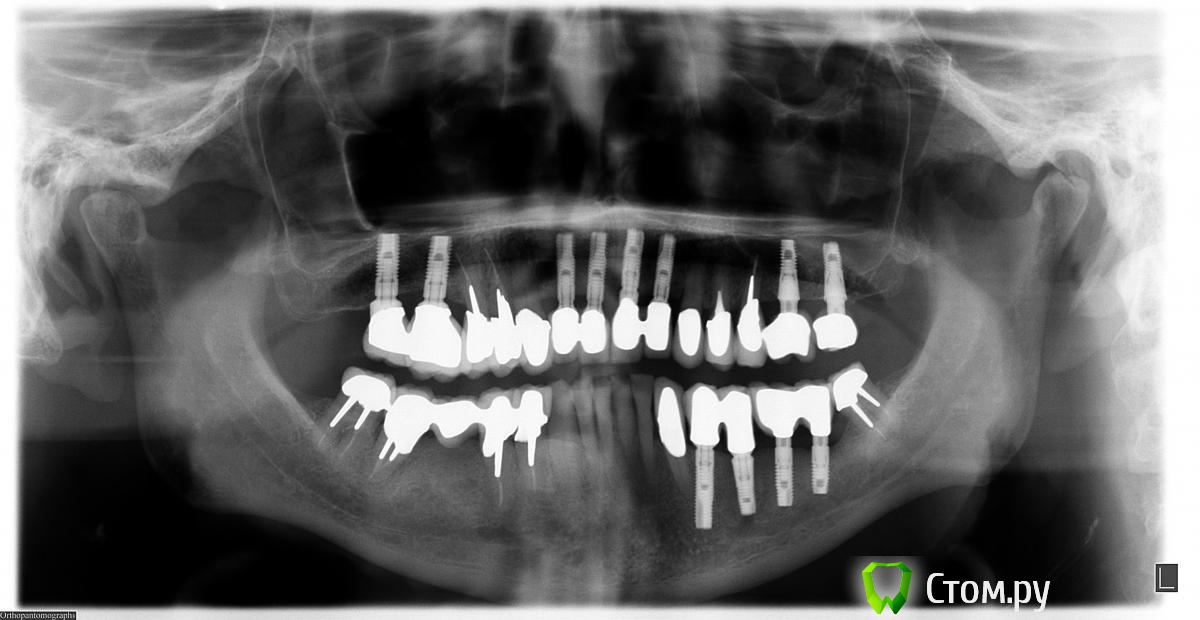

Doc Опубликовано 5 мая, 2014 Поделиться Опубликовано 5 мая, 2014 2004 год, первое посещение. 2004 год, первые имплантаты 2009 год, добавили два имплантата в область 26-27, которые по просьбе пациента были оставлены "без гарантии, пока сами не запросятся наружу", что и случилось через пять лет. Пациент претензий не имел. Сегодня утром, 5 мая 2014 года: По мне так для пациента возраста 68 лет через десять лет упорного жевания картина из серии "дай Бог каждому!". 8 Ссылка на комментарий